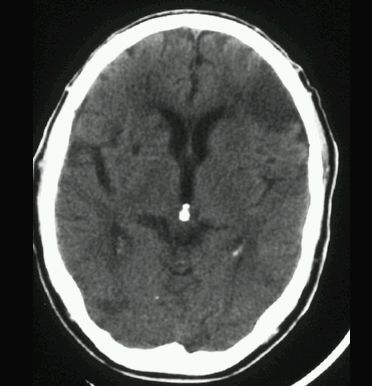

UDAR NIEDOKRWIENNY MÓZGU (ZAWAŁ MÓZGU)

TK